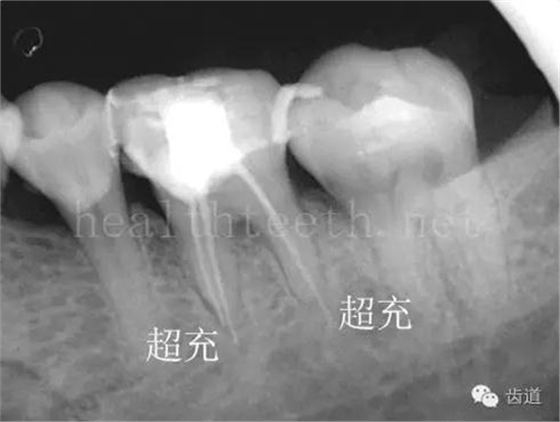

因?yàn)楸旧聿桓阏衬げ?,收集到的病例有限,大多是同事收?/span> 頰粘膜扁平苔蘚 舌粘膜扁平苔蘚 舌緣創(chuàng)傷性潰瘍 長(zhǎng)期戴活動(dòng)義齒不當(dāng)或是戴不良修復(fù)義齒造成的口腔粘膜潰瘍,應(yīng)該引起高度警惕,因?yàn)檫@種潰瘍?nèi)菀装┳?/span> 黑毛舌 舌息肉,該患者同時(shí)伴有胃、食管息肉,后來(lái)看內(nèi)科了,具體情況不詳 四、孩子的牙齒問(wèn)題 乳牙未退,牙根穿出牙齦對(duì)上唇粘膜造成刺激 乳牙滯留,也是孩子在退牙過(guò)程中最容易遇到的問(wèn)題 五、牙齒發(fā)育上的問(wèn)題 變色牙 氟斑牙 釉質(zhì)發(fā)育不全 四環(huán)素牙 牙神經(jīng)治療后的牙齒變色 10歲孩子剛剛萌出的牙齒變色 2、埋伏牙 左上乳3滯留,恒3未見萌出,曲面斷層片顯示牙齒埋伏 通過(guò)CT片確定埋伏牙齒具體的位置,顯示距離左側(cè)上頜竇很近,偏唇側(cè),這為手術(shù)定位提供了方便 手術(shù)中切斷、完整拔出,未損傷上頜竇 其他埋伏牙 3、多生牙 病例1 病例2 病例3,同時(shí)多生兩顆牙齒 4、各種畸形牙 畸形過(guò)小牙 融合牙:恒牙和乳牙都可以發(fā)生融合的情況(兩顆牙齒長(zhǎng)在了一起) 畸形中央尖:在牙齒的中央,兩個(gè)牙尖之間又多長(zhǎng)出一個(gè)牙尖,由于進(jìn)食的磨耗很容易造成磨穿,神經(jīng)就會(huì)與外界相通,出現(xiàn)牙髓炎的癥狀 六、牙齒的外傷 牙冠折斷 牙根折斷 烤瓷牙打樁修復(fù)后牙根折斷 外傷后牙齒的全脫位,應(yīng)該保留牙齒盡早做再植手術(shù) 七、牙齒的慢性損傷 牙頸部楔狀缺損 牙冠劈裂及完整拔除后的情況 牙根縱裂及拔除后的情況 牙隱裂,牙齒表面有肉眼看不到的裂紋,細(xì)菌通過(guò)其進(jìn)入牙髓,容易出現(xiàn)牙髓炎癥狀,嚴(yán)重可以造成牙齒的劈裂 這是一位來(lái)中國(guó)學(xué)習(xí)的俄羅斯大學(xué)生的牙齒,已經(jīng)做過(guò)了根管治療,牙齒咬合面有隱裂,通過(guò)鋼絲結(jié)扎固定,做鑄造金屬冠修復(fù)。 八、牙髓炎、根尖周炎 下面圖片都是慢性根尖周炎的病例,有了齲齒,進(jìn)一步發(fā)展就是牙髓炎,如果此時(shí)沒有得到及時(shí)的治療,疾病會(huì)逐漸發(fā)展破壞到根尖的骨質(zhì),將骨質(zhì)破壞后就在牙齦上出現(xiàn)一個(gè)膿瘺,此時(shí)患者不再感覺到牙齒的疼痛了,往往忽視了治療,但是這種不痛并不是疾病好轉(zhuǎn)了,而是因?yàn)榧膊〉难仔詽B出得到了引流,這個(gè)膿瘺會(huì)出現(xiàn)有時(shí)候變大了,有時(shí)候又變小了,但是如果不治療是不會(huì)自己愈合的,只有經(jīng)過(guò)完善的根管治療后才有好轉(zhuǎn)的可能,但是在疾病的治療中時(shí)間是起決定作用的,時(shí)間拖得越晚,好轉(zhuǎn)的可能性越小,經(jīng)過(guò)根管治療后如果膿瘺還是沒有消失,就需要做根尖刮治術(shù),如果仍然沒有好轉(zhuǎn),就只能做根尖切除術(shù)了,這對(duì)牙齒的穩(wěn)固是不利的。下面圖片中在膿瘺中插入了一個(gè)牙膠尖,是我們做根管充填用的材料,是非常軟的,就是在口腔牙齦瘺管的地方插進(jìn)去,通過(guò)拍牙片可以清晰地看到它到達(dá)的位置,從而確定發(fā)病的牙齒,此處是為了讓大家看得更清楚。 門牙兩個(gè)膿瘺 烤瓷牙修復(fù)后牙齦出現(xiàn)兩個(gè)膿瘺,插入牙膠尖,牙片顯示牙膠尖到達(dá)的位置就是根尖炎癥的位置,根尖骨質(zhì)密度降低(發(fā)黑的地方) 牙齒根尖膿瘺,治療前、中、后的圖片對(duì)照,完善根管治療后膿瘺明顯消失了 牙髓炎和根尖炎治療的關(guān)鍵就是根管治療 合格的根管充填治療 不良的根管充填治療 九、關(guān)于智齒(第八顆牙) 四顆長(zhǎng)不出來(lái)的智齒 智齒反復(fù)發(fā)炎造成的頰瘺,膿腫切開引流后面部會(huì)留疤 智齒造成的頜骨囊腫,手術(shù)切除后需要植骨 十、各種錯(cuò)合畸形 開合 深覆合 深覆蓋,上頜前突 反合(地包天) 牙齒排列擁擠 來(lái)源:牙醫(yī)愛看的 KQ88口腔醫(yī)學(xué)網(wǎng)